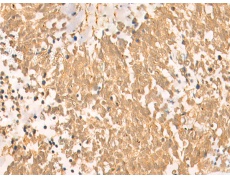

ELISA, IHC |

IHC positive control: |

Human tonsil and Human lung cancer |

IHC Recommend dilution: |

50-300 |